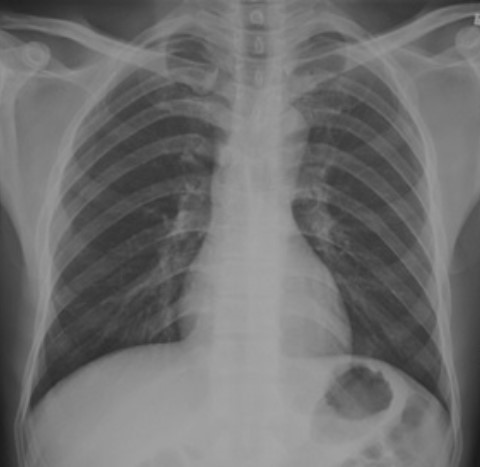

5.根據(jù)下圖請(qǐng)做出正確診斷

A.正常胸片

B.肺門(mén)淋巴結(jié)腫大

C.肺炎

D.主動(dòng)脈型心(靴型心)

答案提示:【該題針對(duì)“ X線-正常胸片 ”知識(shí)點(diǎn)進(jìn)行考核】